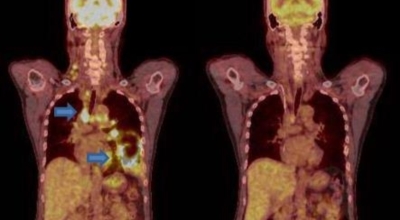

폐암 검사는 X-ray를 통해서 검사하는데 , 크기가 작거나 구석에 위치한 경우 확인이 어려운 경우도 있답니다. 그리고 조직 검사를 통해서 정확한 진단을 하게 되어요. 폐암이 발견되면 종양의 크기나 전이 여부 , 위치에 따라서 수술 여부를 결정하게 됩니다.